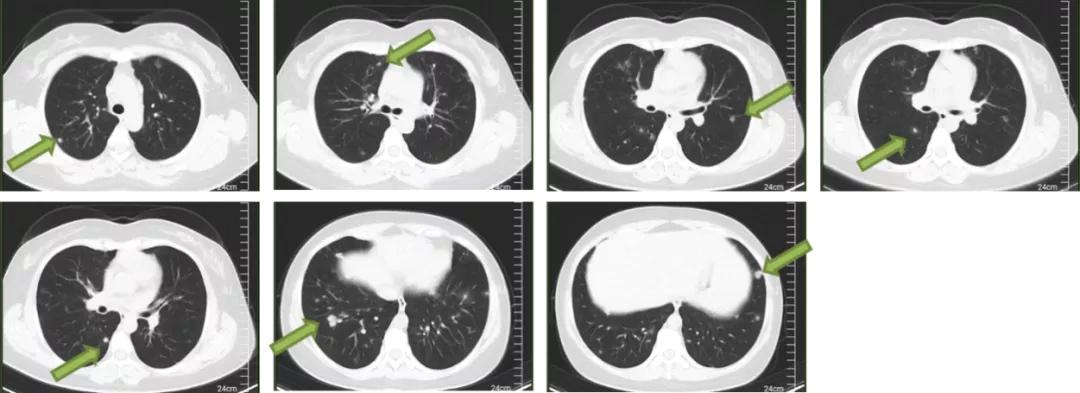

7月14日,患者于当地医院行胸部CT显示两肺多发结节,较4月28日相比有所吸收;纵隔、双侧腋窝小淋巴结;双肺局部少许炎症;脾大,肝内致密影。

图4:胸部CT(2020.07.14)

8月27日于当地医院行胸部CT显示两肺多发结节、絮状影,性质待定,病灶较7月14日相仿;纵隔、双侧腋窝小淋巴结。

图5:胸部CT(2020.08.27)